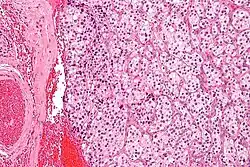

The paragangliomas appear grossly as sharply circumscribed polypoid masses and they have a firm to rubbery consistency. They are highly vascular tumors and may have a deep red color.

On microscopic inspection, the tumor cells are readily recognized. Individual tumor cells are polygonal to oval and are arranged in distinctive cell balls, called Zellballen.[9] These cell balls are separated by fibrovascular stroma and surrounded by sustentacular cells.

Micrograph of a carotid body tumor -